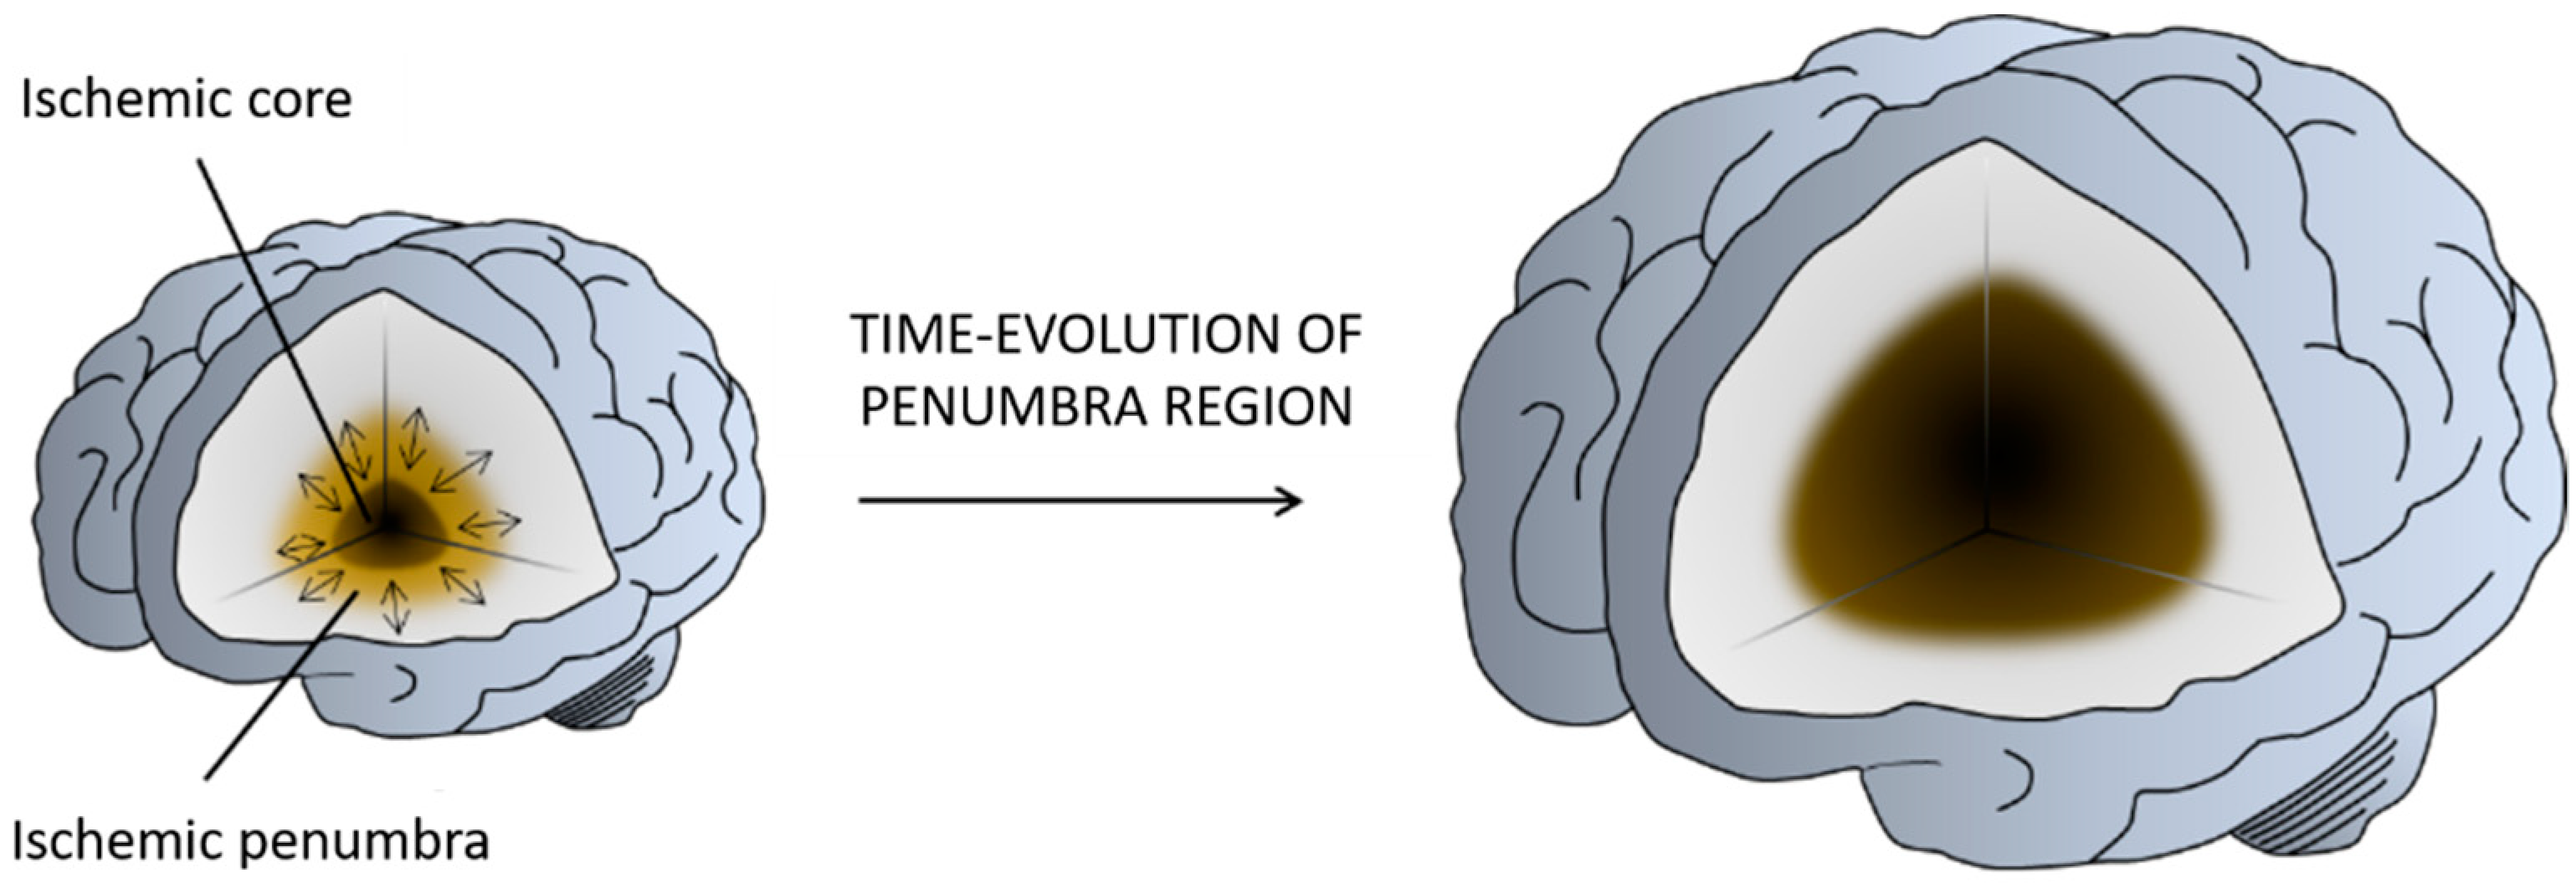

1.1. Stroke

1.2. Nanomedicine